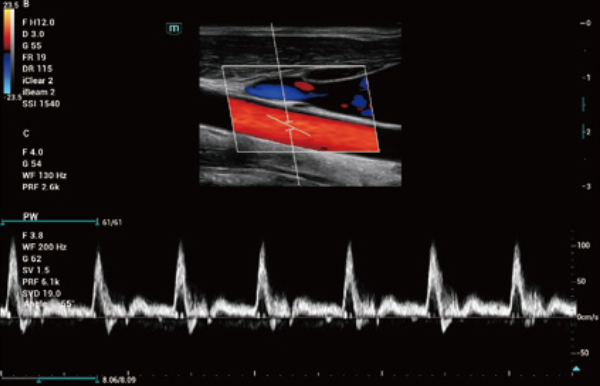

Comprehensive Imaging Solutions Powered by ZST+

The ZST+ platform is an extraordinary innovation, representing an ultrasound evolution. Transforming ultrasound metrics from conventional beam-forming to channel data based processing. It overcomes the traditional trade-off limitation among spatial resolution, temporal resolution and tissue uniformity, delivering exceptional image quality for infinite imaging solutions with non-stop improvements.